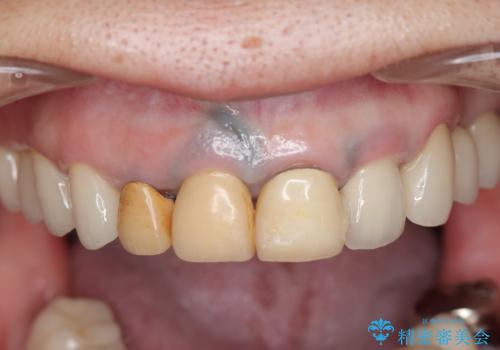

保険適応 硬質レジン前装冠から審美的でオールセラミッククラウンへ

- 変色の進んでしまった前歯を審美的なセラミック治療にしたい、と希望され来院されました。

10数年前に治療を行った保険適応の硬質レジン前装冠は変色劣化が進み、審美的に問題があるだけでなく虫歯のリスクも高くなり好ましくない状況です。

- 39.6万円(ジルコニアクラウン×3・仮歯×3)費用は治療当時の料金となります